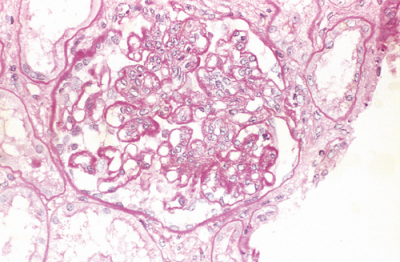

Describe light microscopy of lupus nephritis (DPGN)